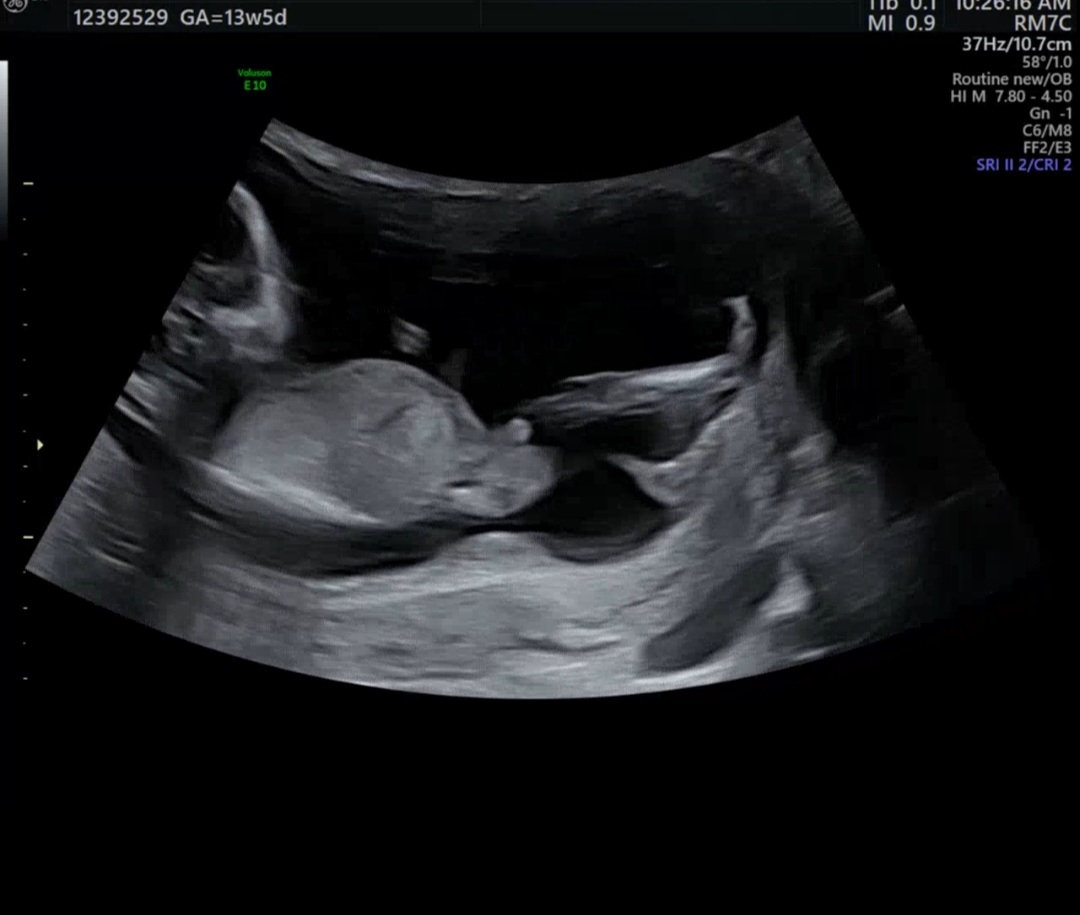

성별이 궁금해요 💭🤍

15주 5일 되었는데 아직 성별을 몰라 이전 초음파 찍었던 영상중에 성별이 확인된 엄마님들께 조언 구하고 싶어요~ 아들일까요? 👼

저도 아들에 한표요 뭔가 튀어나온게 존재감 뿜뿜인데요?! ㅎㅎ

존재감이 딱 보이는같은데요?

아들인거 같아요 ㅎㅎㅎ